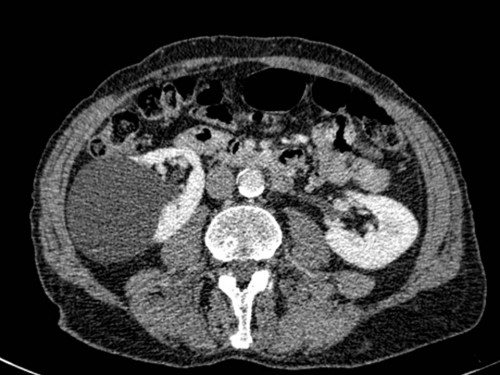

45 Jahre alter Mann.

Bei der Vorbereitung zur Cholezystektomie wurde sonografisch ein abklärungsbedürftiger Befund gesehen.